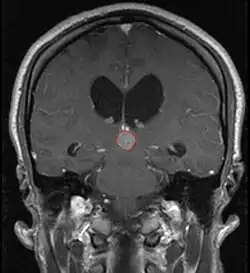

Radiation Oncology/CNS/Pineal

Pineal Gland Tumors

Clinical Presentation

• Determined by the spatial anatomy and direction of growth

• Obstruction of aquaduct: hydrocephalus presenting as headaches, nausea, vomiting

• Compromise of superior colliculus: vertical gaze palsy, pupillary and oculomotor nerve paresis (Parinaud syndrome)

• Work-up includes MRI, CSF, serum markers for bHCG and AFP

• Tissue diagnosis is critical, since management varies significantly based on pathology